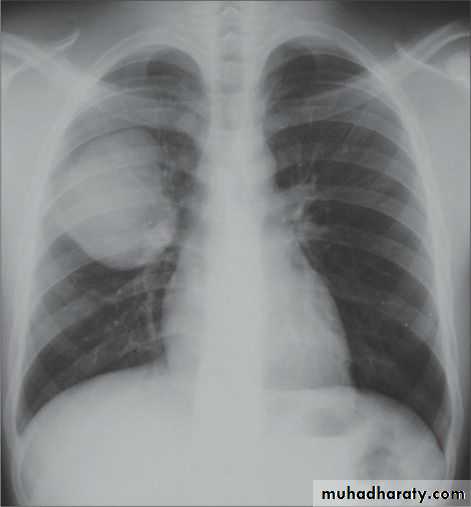

(Collapse) (Massive plural effusion)